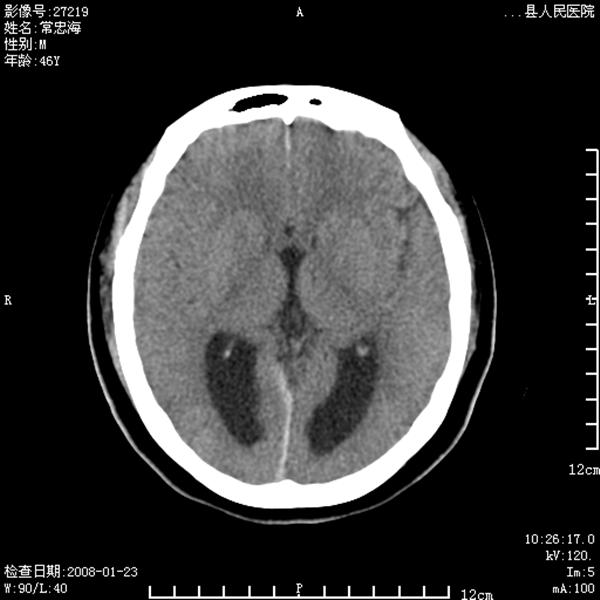

以下是引用江边学者在2008-4-19 22:26:00的发言:[br]1.胼胝体发育不良。[br]2.右侧眼球痨。[br]3.右侧颜面部软组织挫伤。